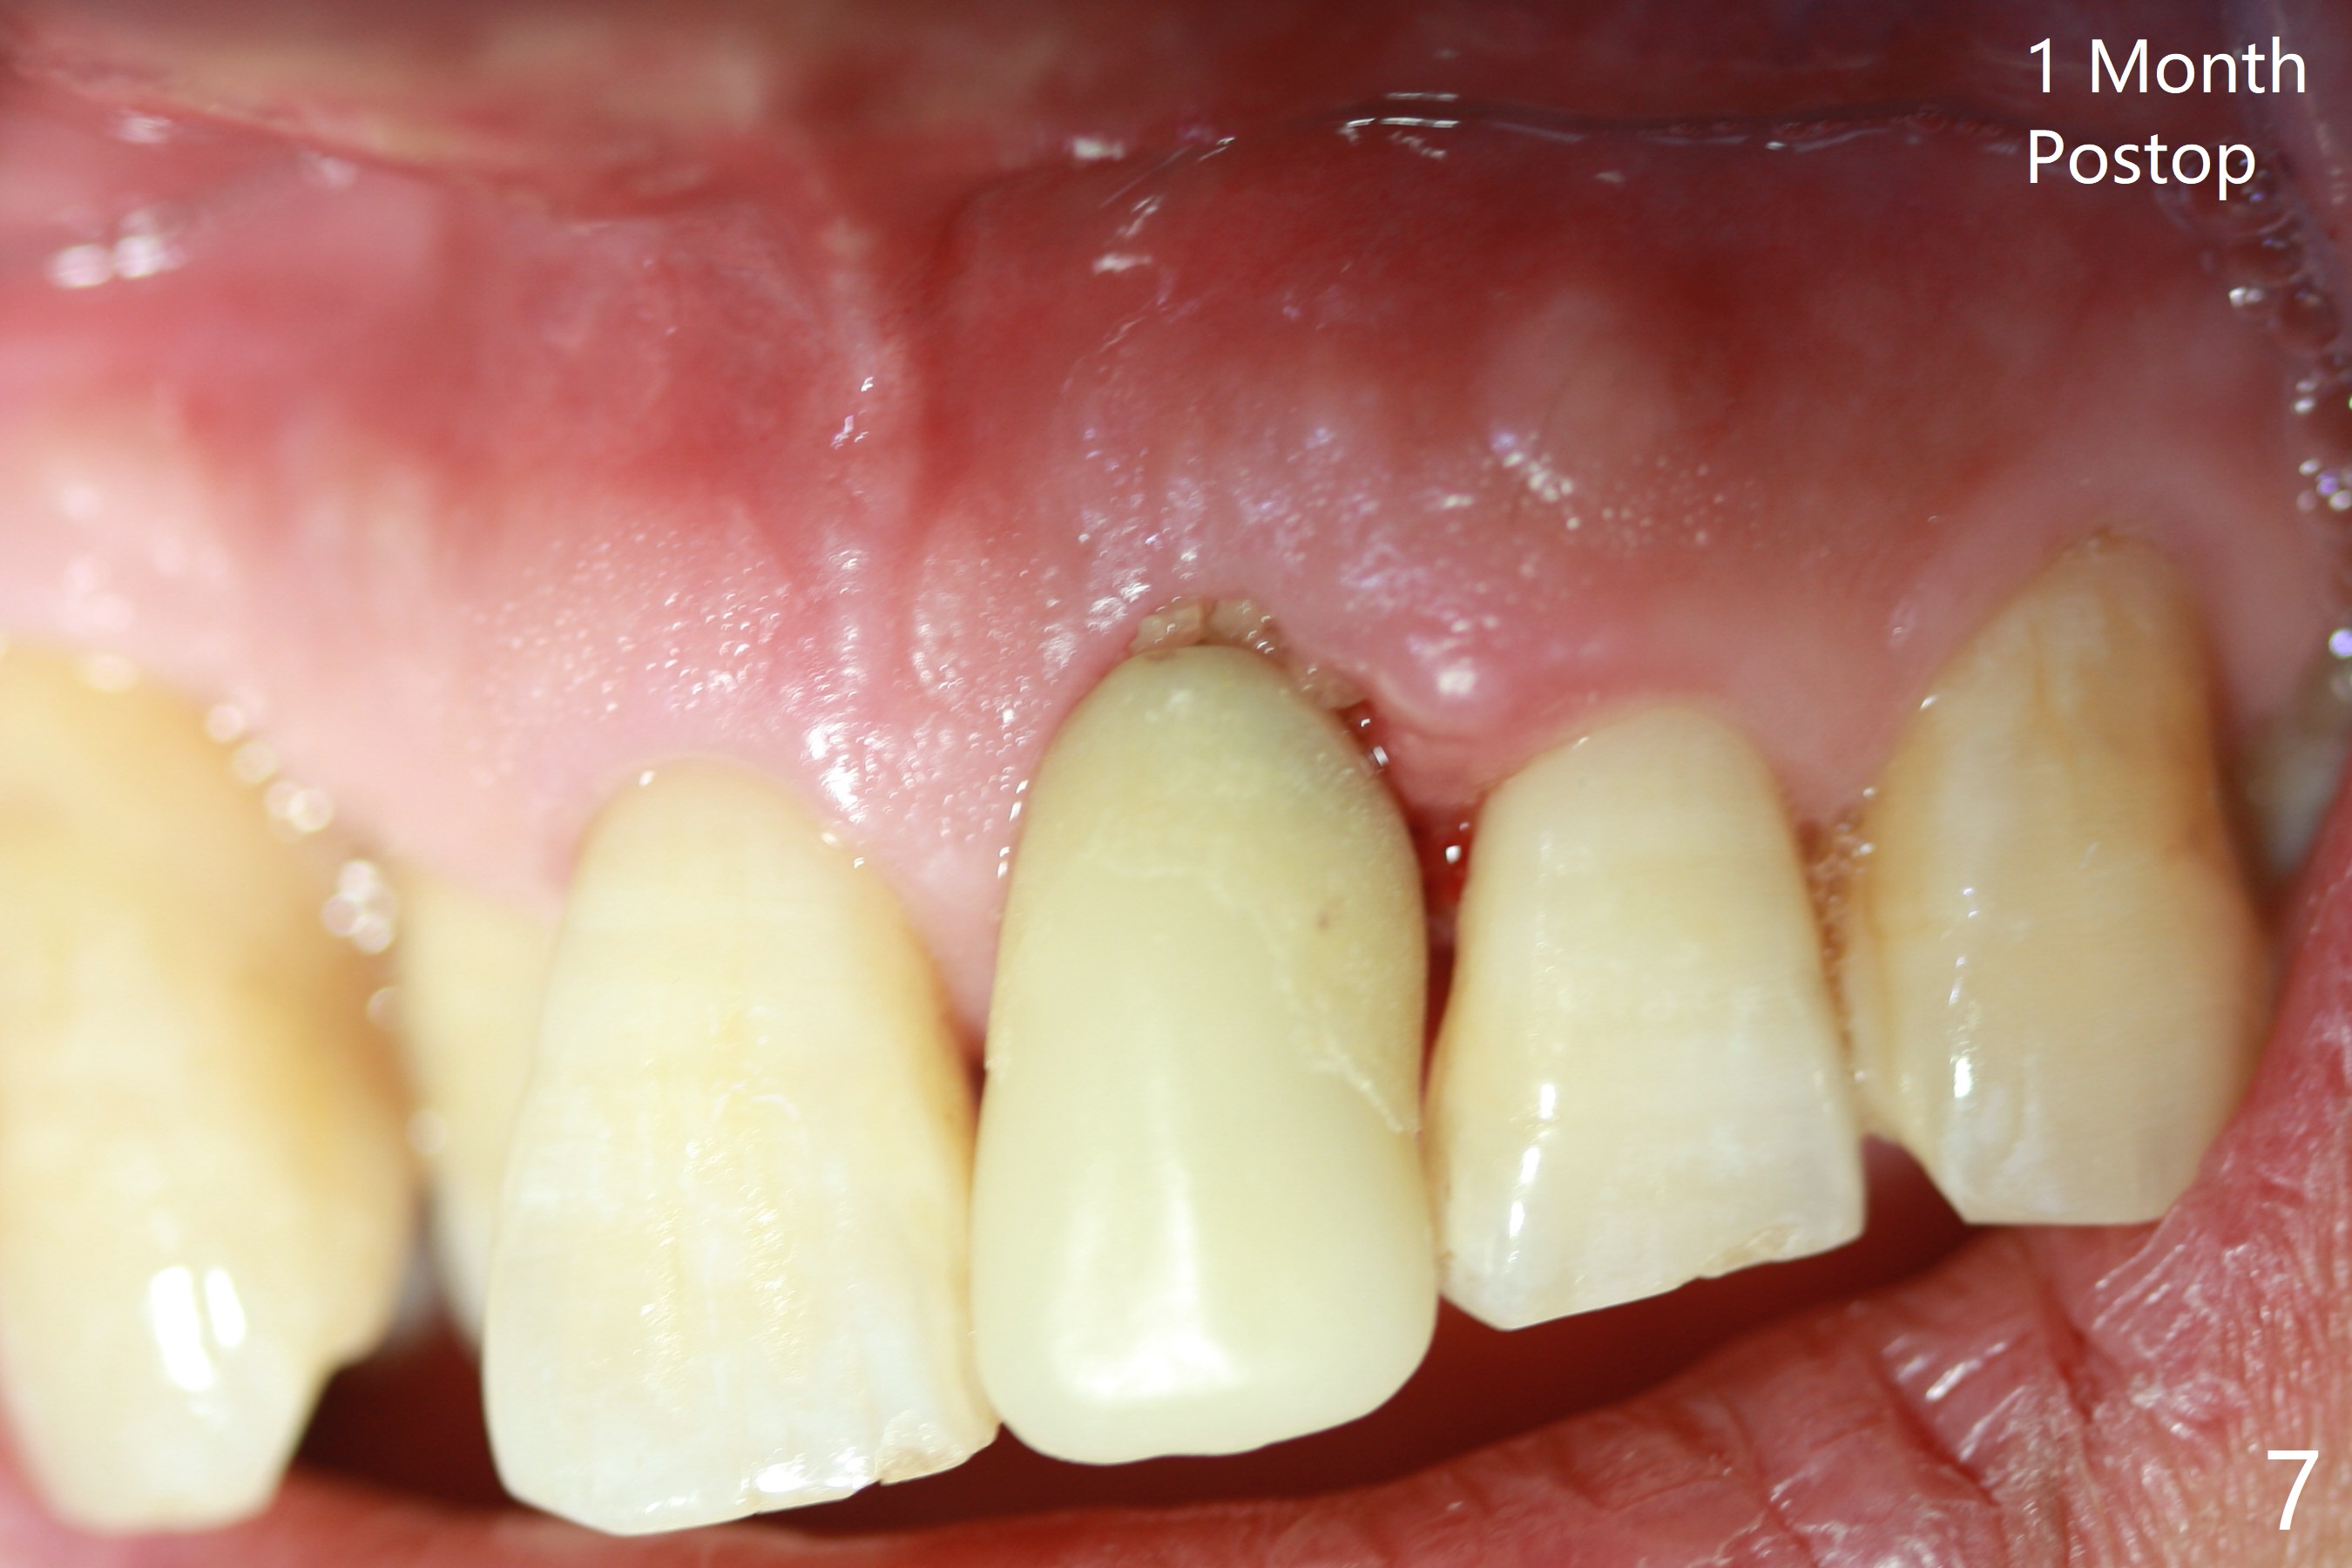

Immediately preop PA confirms loss of the buccal plate at #9 (Fig.1 *). In contrast the palatal crest is ~ 4 mm subgingival (WNL) after extraction. When initial osteotomy reaches 18 mm, there is moderate hemorrhage, probably due to close to the nasal floor (Fig.2 red dashed line). Following sequential osteotomy, a 3.8x15 mm dummy implant is placed partially (Fig.3 (pink: apical osteotomy)). After placement of an implant with the same dimension as the dummy's (Fig.4), PRF is laid against the inner surface of the buccal defect and allograft (Fig.5 *) is packed mainly in the buccal gap before and after insertion of a 4.5x5(4) mm abutment. The patient is satisfied with the immediate provisional (Fig.6: 1 week postop). The buccal margin of the provisional is shortened with exposure of bone graft to facilitate gingival downgrowth (Fig.6: 1 month postop). The buccal plate seems to collapse nearly 2 months postop (Fig.8 *), probably due to loss of the bone graft. The abutment is exposed buccally (Fig.9). The margin of the abutment is reprep and the provisional is relined so that the margin of the provisional is palatal to the buccal gingival margin. In 2-3 weeks, a temporary abutment will be used to bulk the buccal gingiva. The gingiva seems to have downgrown; the buccal plate collapse appears normal nearly 3 months postop (Fig.10). The patient is more concerned about cross bite at #7. A temporary abutment is not used. The bone graft remains in place 3.5 and 4.5 months postop (Fig.11,12 *). Between 3 and 4 months postop, the mesial surface of the abutment has been trimmed (Fig.12 >). Since the mesial surface of the tooth #10 will be reduced (white curved line) to correct the upper dental midline, an angled abutment (red line) seems to be necessary to shift the provisional distal.